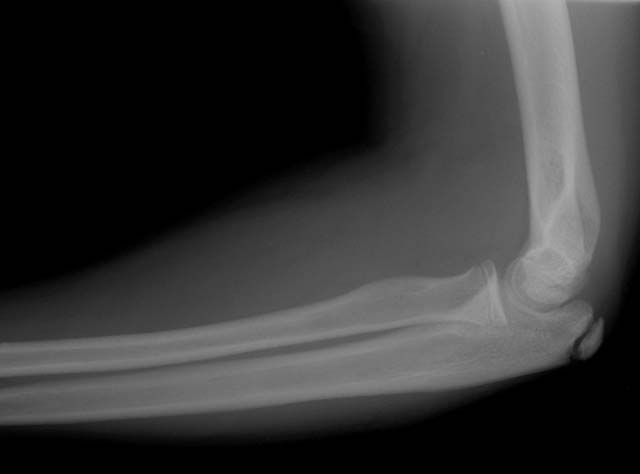

Elbow x-ray (lateral)